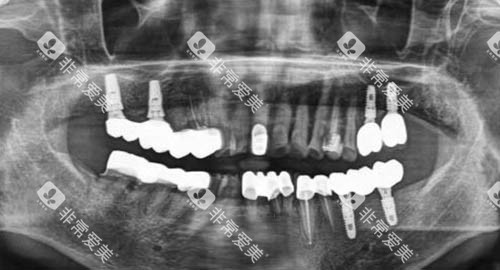

如智能化口腔全景机,能够快速、较准地拍摄口腔全景图像,帮助医生多方面了解患者的口腔状况;口腔种植机则采用了较高的种植技术,大大提高了种植牙的成功概率和稳定性。